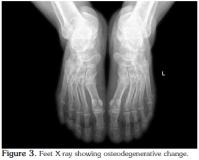

The bilateral knee radiographs of the patient were normal (Figure 2), but those of the feet revealed osteodegenerative changes (Figure 3) and bilateral heel spurs (Figure 4).